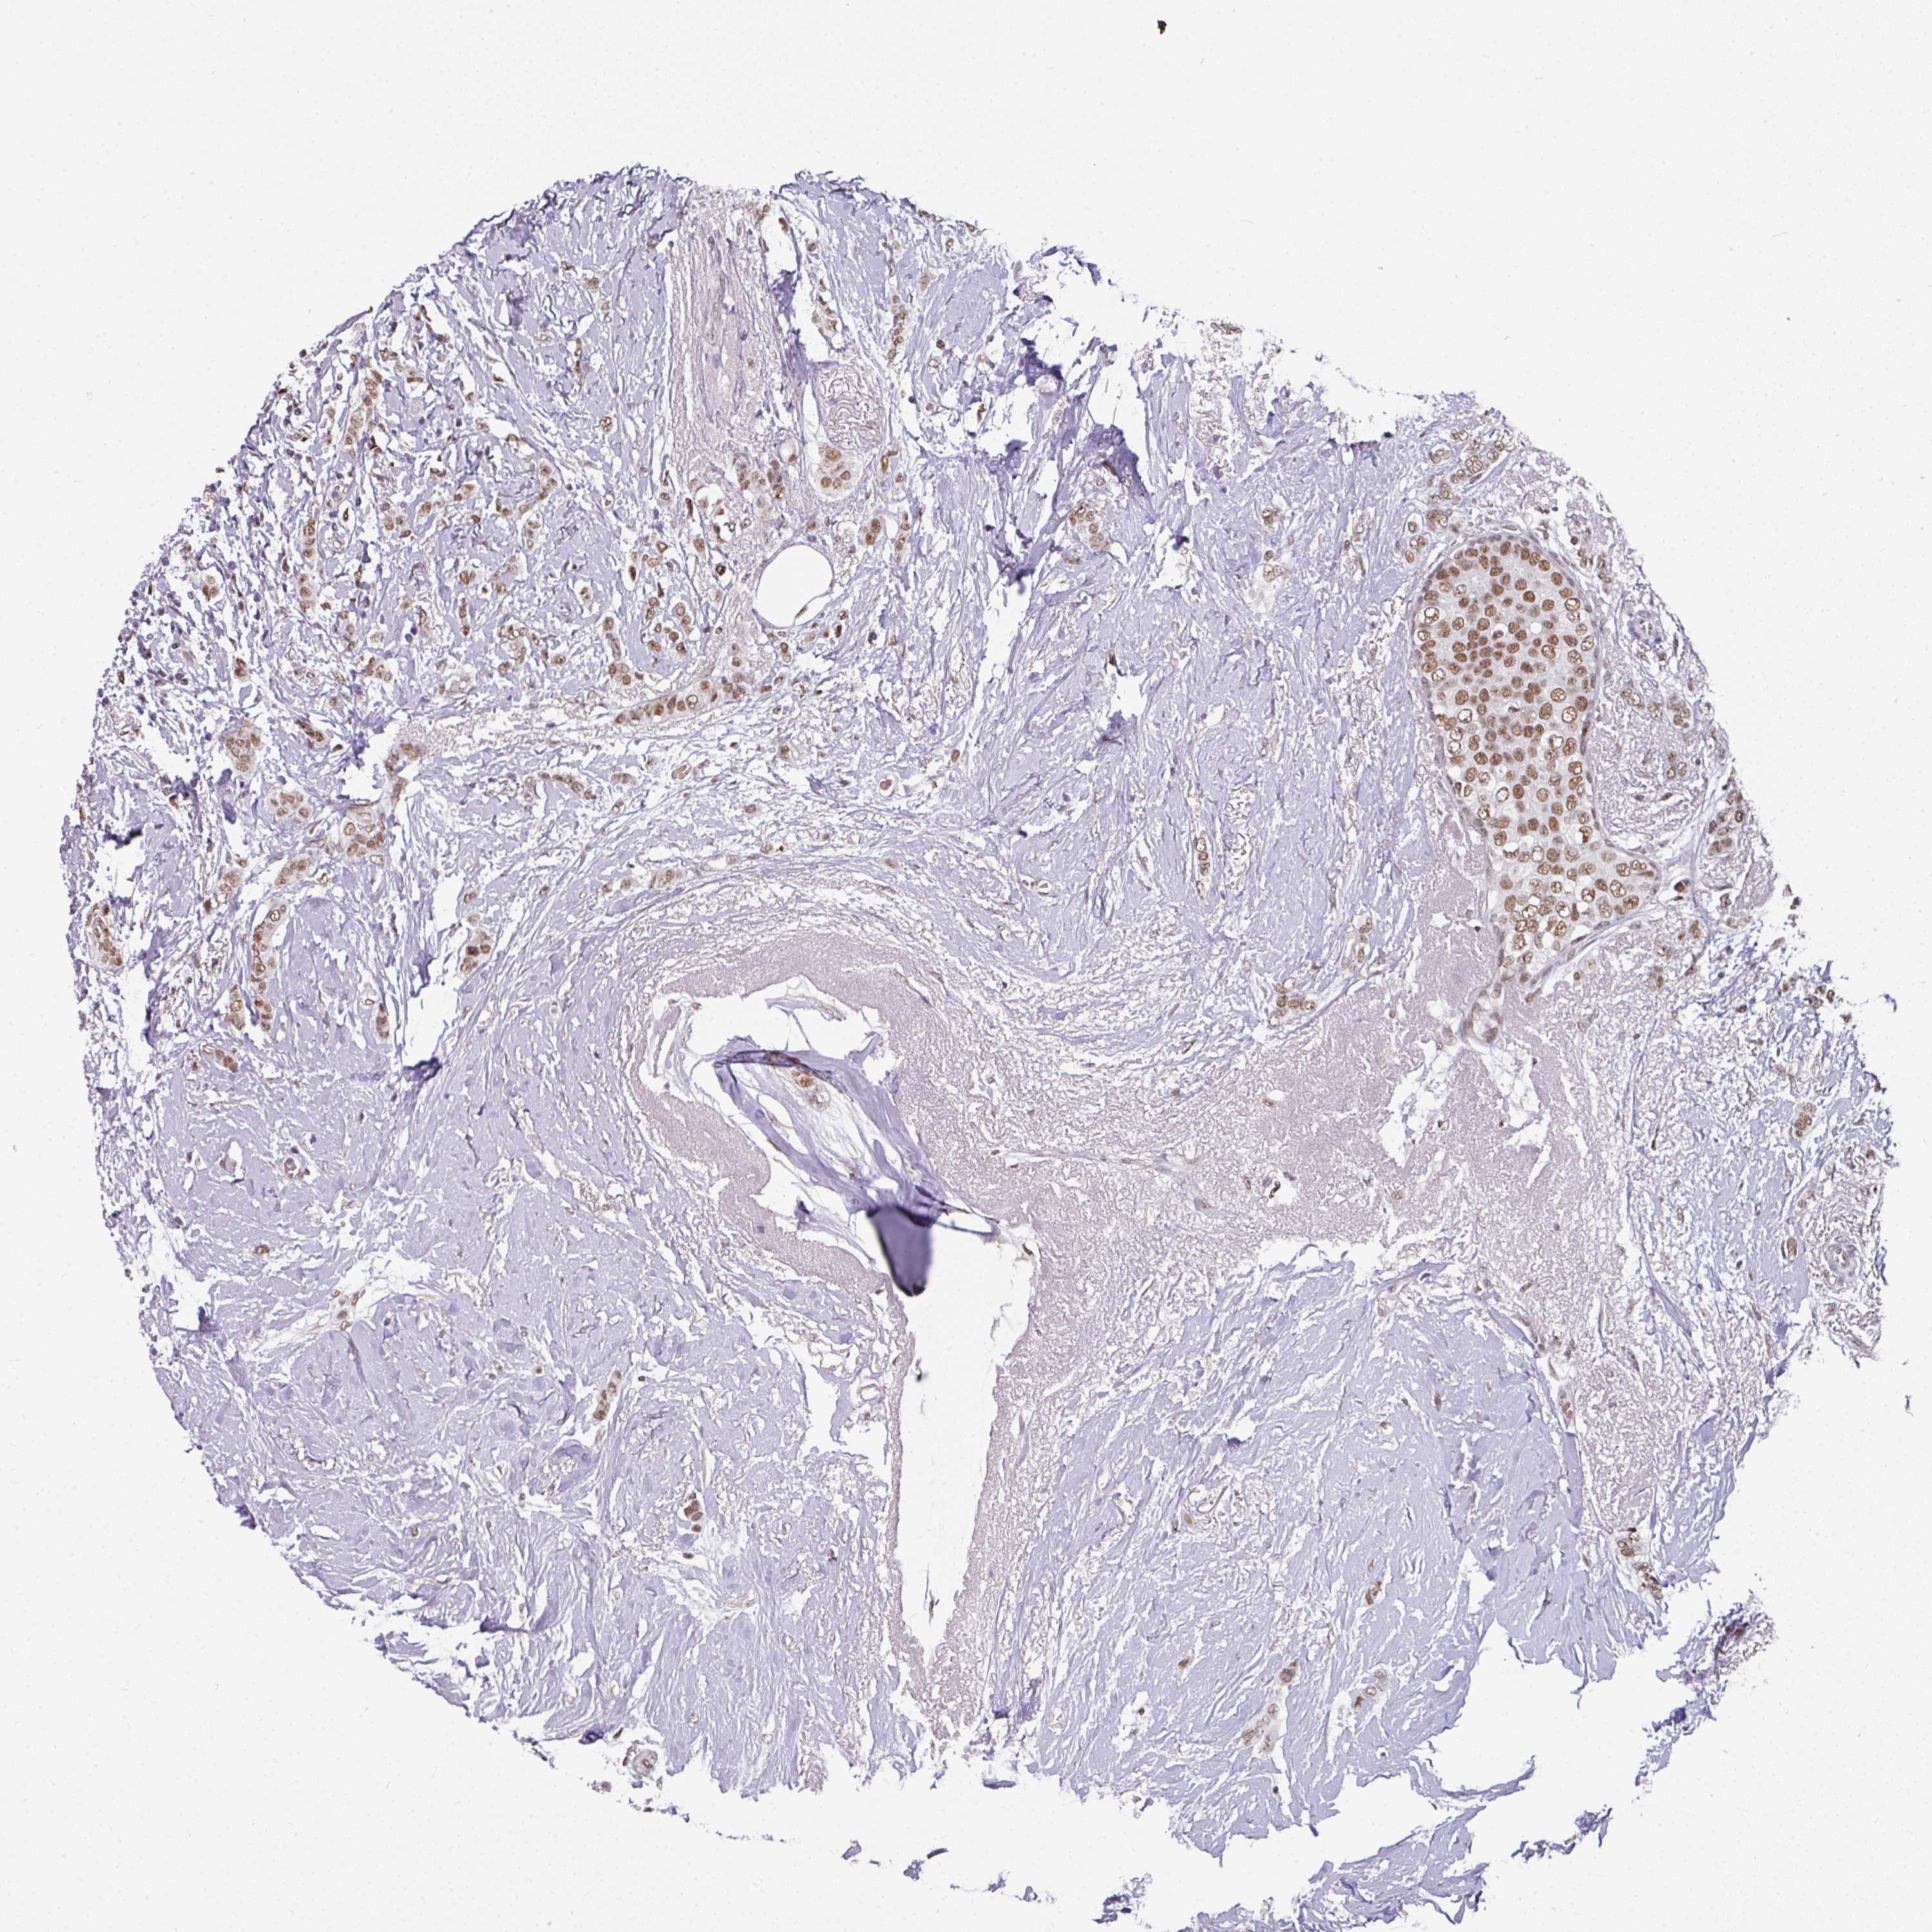

BRCA TCGA BRCA VALIDATION PROTEIN EXPRESSION